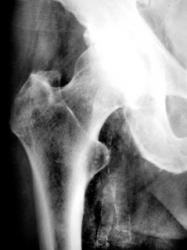

Пациентка 52 лет направлена на рентгенологическое исследование врачом хирургом с диагнозом «Двусторонний коксартроз». Произведено стандартное исследование тазобедренных суставов в прямой стандартной проекции.

На рентгенограмме левого тазобедренного сустава – иллюстрация 1 определяется умеренно выраженный субхондральный склероз в области верхне-наружного отдела вертлужной впадины. Также определяется незначительное сужение суставной щели в верхне-наружном отделе.